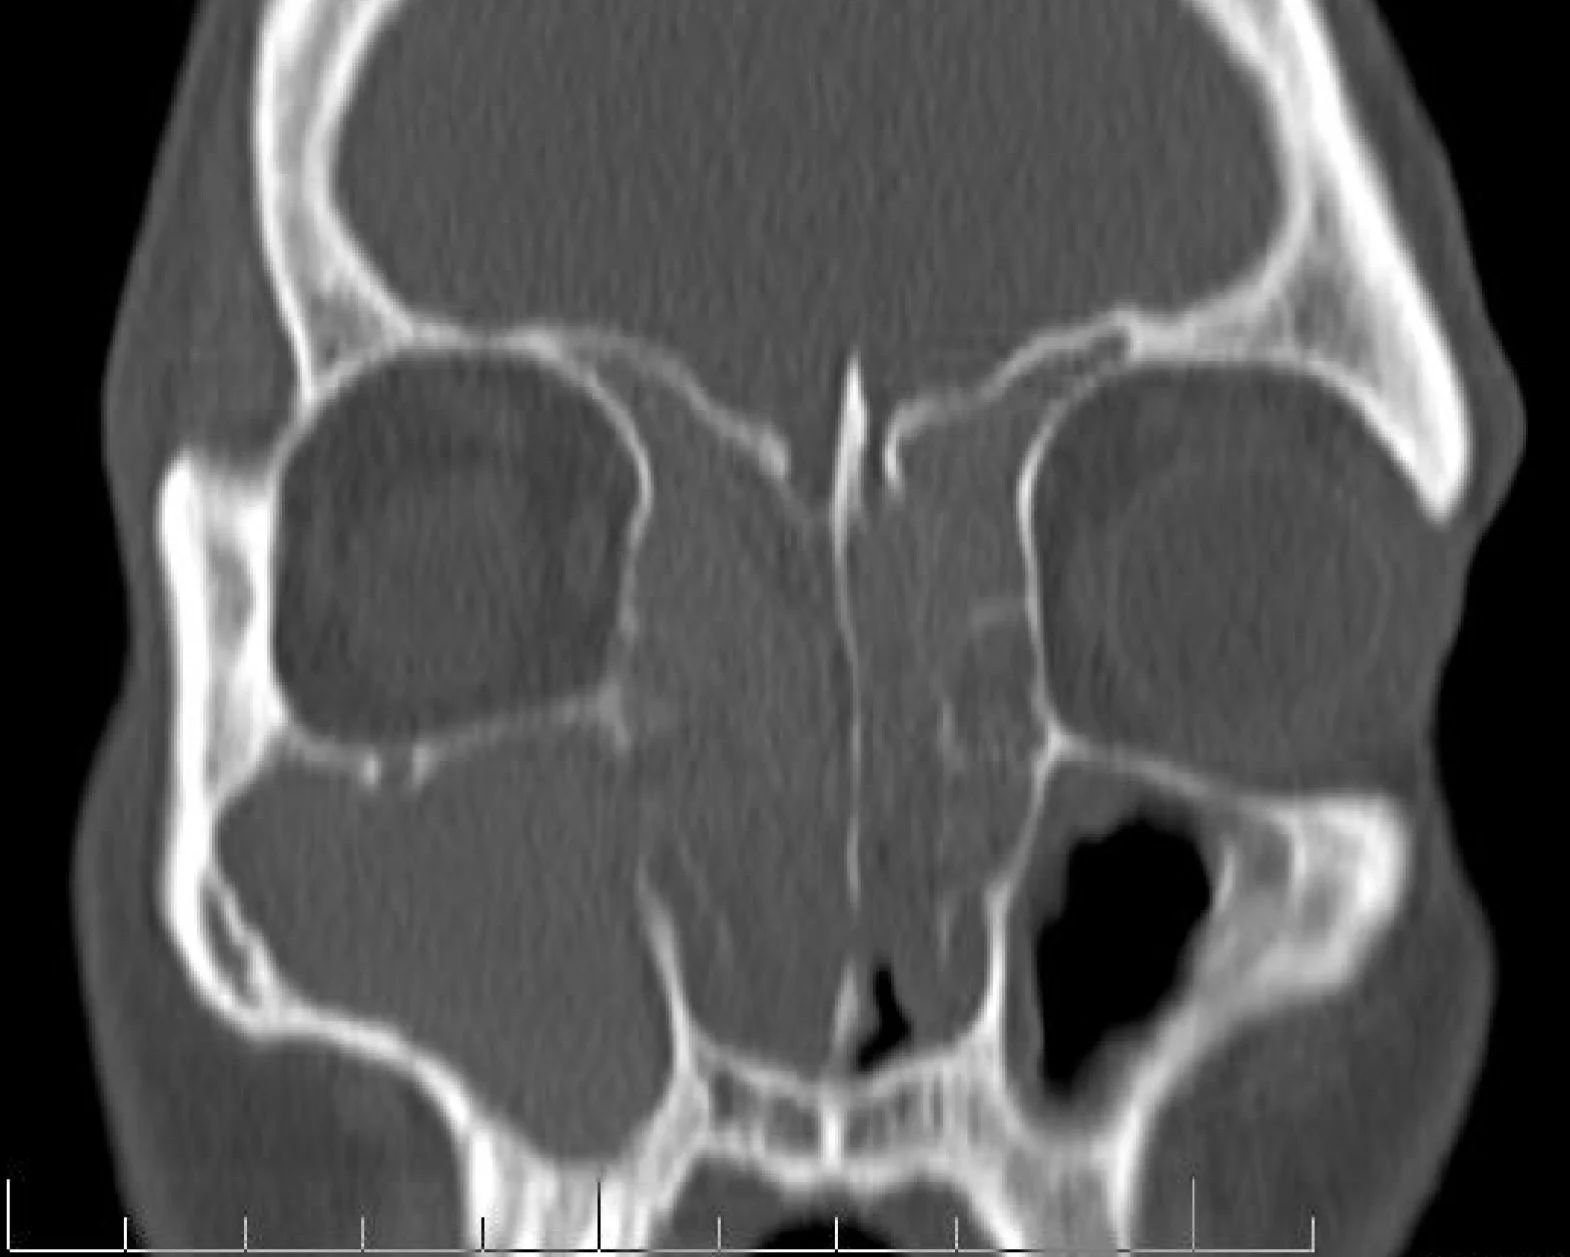

Do I Need a CT Sinus Scan?

If sinus infections or congestion keep coming back, a quick in-office CT scan can reveal the root cause and spare you multiple appointments, extra driving, and lost time.